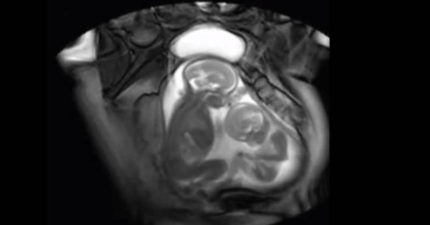

研究者想利用MRI檢查雙胞胎胎兒情況,沒想到意外拍下「雙胞胎打架畫面」讓有兄弟姊妹的人都笑翻了!